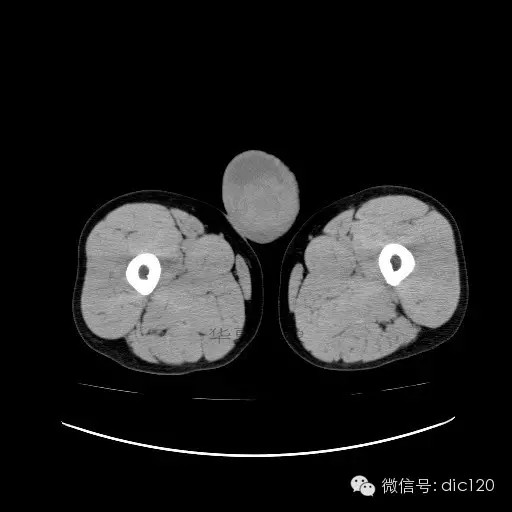

【影像表现】

青年男性,右侧睾丸肿大,边界清晰,增强后睾丸不均匀中度强化,内可见多灶囊变坏死区,动脉期肿块内有细小动脉血管显示,延迟期可见分隔样强化,鞘膜囊可见积液。

定位定性:右侧睾丸恶性肿瘤。

【影像诊断】

右侧睾丸精原细胞瘤,右侧睾丸鞘膜积液。